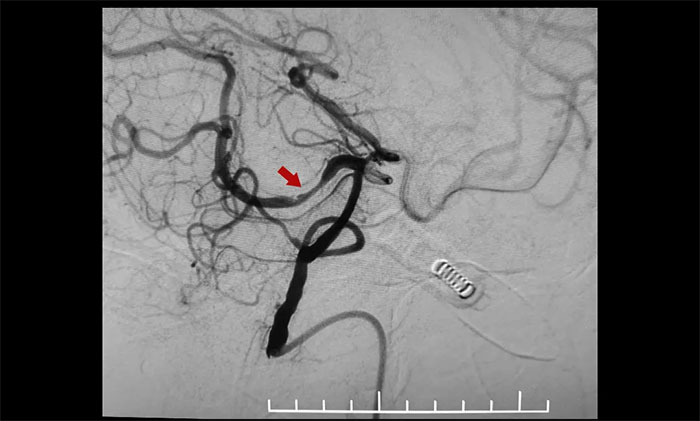

術(shù)中,通過輸送型球囊擴張微導管輕松越過狹窄病變,完成右側(cè)大腦后動脈狹窄段的球囊擴張及支架置入等步驟,無需進行微導管交換、球囊交換以及支架微導管交換的過程。手術(shù)治療部分僅耗時30分鐘。術(shù)后造影顯示右側(cè)大腦后動脈P1、P2交界段重度狹窄明顯改善。行支架CT見支架成形良好。

▲ 術(shù)前,右側(cè)大腦后動脈重度狹窄

▲ 術(shù)后,右側(cè)大腦后動脈狹窄明顯改善